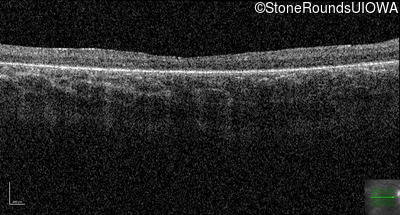

Age at visit: 10 years

OD OS

Age at visit: 11 years

Age at visit: 12 years

Age at visit: 13 years

Age at visit: 14 years

Age at visit: 16 years